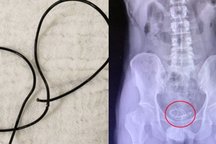

Qua thăm khám, dựa trên các xét nghiệm siêu âm và phim chụp X-quang, các bác sĩ phát hiện ra một đoạn keo nến cuộn trong bàng quang và một phần tại niệu đạo.

Các bác sĩ đã nội soi bàng quang để lấy dị vật ra ngoài cho bệnh nhân. Kết quả, đã lấy được một cây keo nến đã bị gãy thành 3 đoạn, với tổng chiều dài 40cm. Bên cạnh đó, trong khi thực hiện lấy bỏ dị vật ra ngoài, bác sĩ nhận thấy niêm mạc bàng quang, và niệu đạo đã có hiện tượng viêm đỏ. Một vài điểm có tổn thương niêm mạc niệu đạo.

Dị vật là cây keo nến được lấy ra từ niệu đạo của bệnh nhân (Ảnh: L.N).